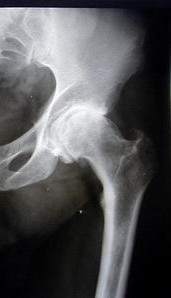

Una diagnosi di coxartrosi comincia con una visita specialistica ortopedica, che deve essere completata da un esame radiografico che evidenzierà l’entità della degenerazione artrosica e talvolta, per studiare dettagli aggiuntivi, da una risonanza magnetica o una TC; altri test (esami ematici, etc.) possono essere richiesti qualora ci sia ragione di credere che altre condizioni (artrite reumatoide, processi infiammatori) contribuiscono al processo degenerativo. Ove l’artrosi e la sintomatologia correlata fosse grave, l’indicazione chirurgica è una protesi di anca.